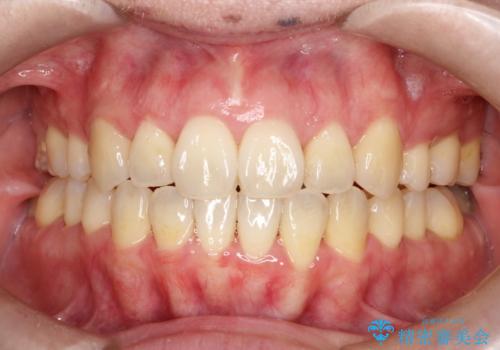

- 50代の患者様で、右上の八重歯と歯並びの乱れを気にされてご来院されました。特に、すでに装着されている前歯のセラミックブリッジを外したくないという強いご希望がありました。精密な検査の結果、八重歯を治すためのスペースが不足しているため、右上の4番目の歯(小臼歯)を抜歯し、そのスペースを利用して歯並び全体を整える治療計画を立案。装置には目立たないインビザラインを採用し、ブリッジを温存しながら八重歯の改善を目指しました。